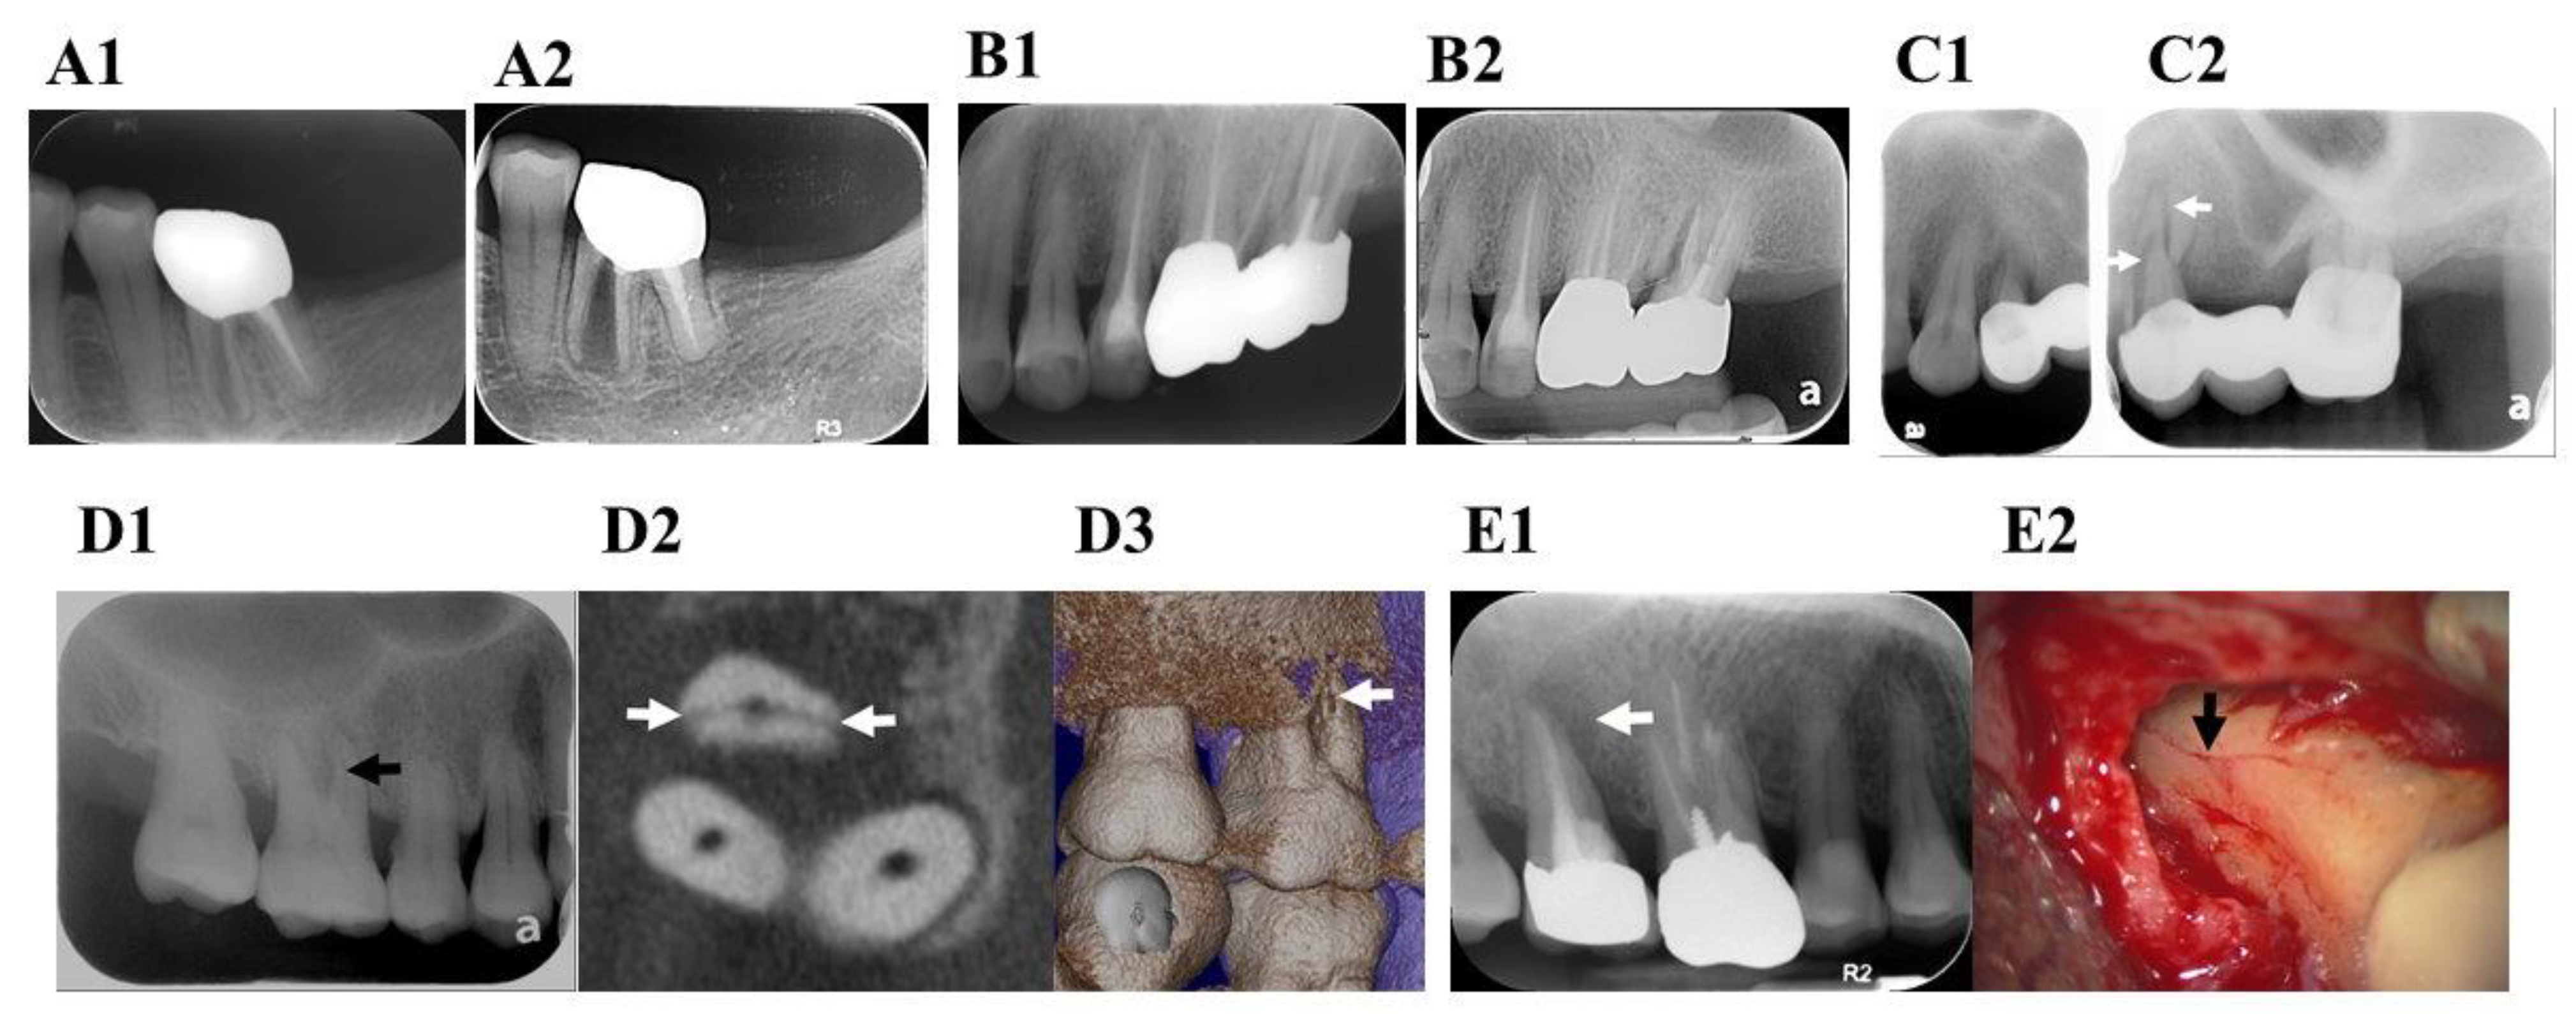

9. Radiographic Characteristics

9.1. Displacement of Fractured Fragment

9.2. Radiolucent Line within the Root Canal

9.3. Unusual Space between the Canal Wall and Intracanal Material

9.4. Widening PDL Space

9.5. Periradicular Radiolucent Halo

9.6. Angular Bony Destruction

9.7. Step-Like Bone Defect

9.8. V-Shaped Diffuse Bone Defect

9.9. Root Resorption Correspond to the Fracture Line (Figure 5F1,F2)

9.10. Widening of the Root Canal Space (Figure 5G)

9.11. Endodontic Failure after Healing has Occurred

9.12. No Evident Radiographic Finding